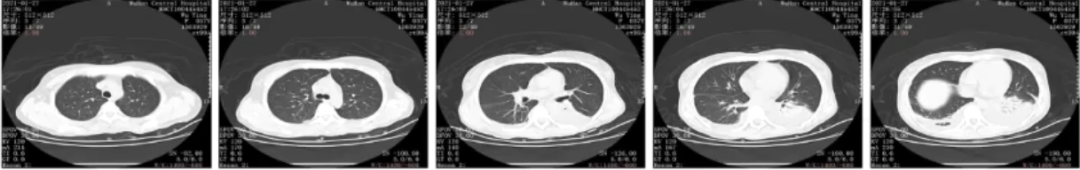

患者1月18日胸部CT基本正常,但1月20日胸部CT示两肺多发实变伴结节影(图1)。

图1 患者入RICU前后胸部CT对比